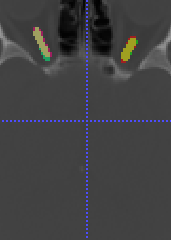

In Chapter 6, we propose an end-to-end, atlas-free 3D convolutional deep learning framework for fast and fully automated whole-volume HaN anatomy segmentation [115]. Our deep learning model, called AnatomyNet, segments OARs from head and neck CT images in an end-to-end fashion, receiving whole-volume HaN CT images as input and generating masks of all OARs of interest in one shot. AnatomyNet is built upon the popular 3D U-net architecture, but extends it in three important ways: 1) a new encoding scheme to allow auto-segmentation on whole-volume CT images instead of local patches or subsets of slices, 2) incorporating 3D squeeze-and-excitation residual blocks in encoding layers for better feature representation, and 3) a new loss function combining Dice scores and focal loss to facilitate the training of the neural model. These features are designed to address two main challenges in deep-learning-based HaN segmentation: a) segmenting small anatomies (i.e., optic chiasm and optic nerves) occupying only a few slices, and b) training with inconsistent data annotations with missing ground truth for some anatomical structures. We collect 261 HaN CT images to train AnatomyNet, and use MICCAI Head and Neck Auto Segmentation Challenge 2015 as a benchmark dataset to evaluate the performance of AnatomyNet. The objective is to segment nine anatomies: brain stem, chiasm, mandible, optic nerve left, optic nerve right, parotid gland left, parotid gland right, submandibular gland left, and submandibular gland right. Compared to previous state-of-the-art results from the MICCAI 2015 competition, AnatomyNet increases Dice similarity coefficient by 3.3% on average. AnatomyNet takes about 0.12 seconds to fully segment a head and neck CT image of dimension , significantly faster than previous methods. In addition, the model is able to process whole-volume CT images and delineate all OARs in one pass, requiring little pre- or post-processing. We demonstrate that our proposed model can improve segmentation accuracy and simplify the auto-segmentation pipeline. These contributions are released as an open-source software package called AnatomyNet, which is publicly available555https://github.com/wentaozhu/AnatomyNet-for-anatomical-segmentation. Portions of this chapter were published as part of [115].